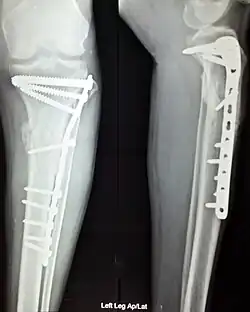

Orthopedic surgery or orthopedics (alternative spelling orthopaedics) is the branch of surgery concerned with conditions involving the musculoskeletal system.[1] Orthopedic surgeons use both surgical and nonsurgical means to treat musculoskeletal trauma, spine diseases, sports injuries, degenerative diseases, infections, tumors and congenital disorders.

- Repair of femoral shaft fracture